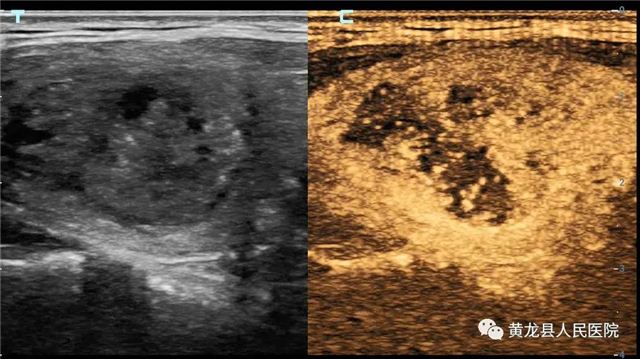

甲状腺结节术前造影

甲状腺结节术后造影